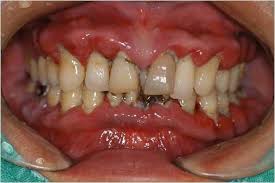

잇몸이 소실되는 가장 흔한 원인은 바로 **치주 질환**입니다. 치주 질환은 치아 주위 조직에 염증이 생기는 질환으로, 초기에는 잇몸이 붓고 피가 나는 치은염으로 시작해, 점차 잇몸뼈까지 녹아내리는 치주염으로 발전합니다. 치주염이 심해지면 잇몸이 내려앉아 치아 뿌리가 노출되고, 결국 치아를 지지하는 잇몸뼈가 소실되어 치아가 흔들리거나 빠질 수도 있습니다.

잇몸이 소실된 경우, 현대 치의학은 다양한 방법으로 잇몸을 재건하거나 그 기능을 회복시키는 데 도움을 줍니다. 주요 술식으로는 크게 잇몸 조직을 재건하는 **치은 이식술**과 잇몸뼈를 재건하는 **골 이식술(치조골 이식술)**, 그리고 **조직유도재생술(GTR)** 등이 있습니다.

첫 번째로, **치은 이식술**은 잇몸이 부족하여 치아 뿌리가 노출되거나 시린 증상이 있을 때 주로 시행됩니다. 환자 본인의 입천장이나 다른 부위에서 건강한 잇몸 조직을 채취하여, 잇몸이 소실된 부위에 이식하는 방법입니다. 이를 통해 노출된 치아 뿌리를 덮고 잇몸의 높이와 두께를 회복하여 심미적인 개선뿐만 아니라 시린 증상 완화에도 도움을 줍니다.